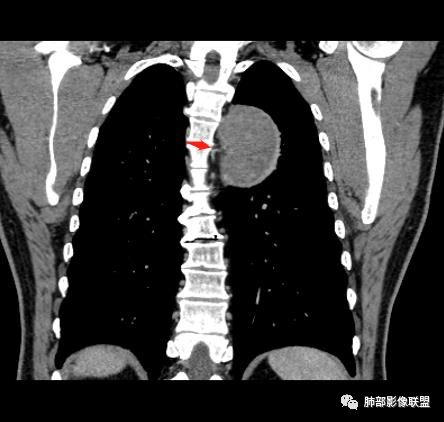

红日东升:左侧胸椎旁肿块,边缘清晰光整,冠状位见D字征,未见支气管进入,肺组织受压表现,定位肺外。轻度强化,密度稍不均匀,临近肋骨变细,未见肺动脉供血,考虑良性肿瘤,神经源性可能。右肺下叶病灶,轻度强化,血管显影,边缘平直、凹陷,考虑炎性病变。

张立:左侧胸椎旁肿块,边缘清晰光整,冠状位见D字征,未见支气管进入,肺组织受压表现,定位肺外。轻度强化,密度稍不均匀,,未见肺动脉供血,神经源性肿瘤,节细胞神经瘤可能。右肺下叶病灶,轻度强化,血管显影,边缘平直、凹陷,TB可能。

崇军:左侧胸椎旁肿块,边缘清晰光整,有胸膜尾征,冠状位为D字征,定位肺外。轻度强化,密度稍不均匀,似乎看到肋间动脉供血,未见肺动脉供血,考虑良性肿瘤,神经源性可能。右肺下叶病灶,轻度强化,血管显影,边缘平直、凹陷,层面太少,暂时考虑炎性病变。

长沟流月去无声:中年男性,慢咳起病,左后纵隔可见一大占位,D字征,胸膜掀起,有胸膜尾征,附近肺组织受挤压,血管纹理纠集,瘤肺界面清晰,较均匀轻-中度强化,瘤肺表面可见线样不张之强化影,供血血管来源不易确定,冠状位似乎见一纵隔血管出入,综合考虑神经源性肿瘤:神经纤维瘤,神经鞘瘤?右下外斑片密度影,估计炎性,但本次手术应该未处理。

ZK金:定位:左肺下叶后综合脊柱旁肺外肿块,胸膜尾征,D字征,瘤肺交界面清晰,肺组织受压。影像表现:边界清晰,密度均匀,上下经线略横经。首先考虑神经源性肿瘤,神经节细胞瘤首选,鞘瘤和孤立性纤维瘤鉴别诊断。右肺下叶考虑炎症。

椎间孔很有价值吧

如果椎间孔增大,应该考虑神经源性的

大雄:所以还是得看潘老师说的椎间孔

问题是大病灶,而且椎间孔没累及

5.相邻椎间孔未见扩大,也未见块影延入椎管,易起自于神经根的鞘瘤似乎找不到相关支持点。

6.未提供矢状位骨窗图像,如在肋骨内下缘观察到压迹有助于肋间神经的鞘瘤的判断,这是因为二者之间密切的毗邻关系。